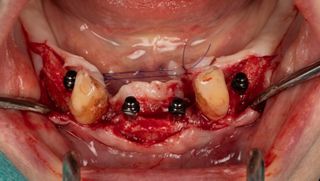

3a. Elevation of the full-thickness flap by crestal incision centred on the keratinised and sulcular tissues in 33 and 43.

The canines are preserved to provide an indication of the drilling axis.

Initial drilling in 32 and 42 using the first 1.5 mm drill bit, then positioning of directional indicators to assist with subsequent drilling. Drilling to 12 mm is checked using the graduation on the initial drill bit.

3a

3b

3b. Drilling adjacent to the remaining teeth 33 and 43 using the initial 1.5 mm drill. Depth and axis checked using the anterior indicators and residual canines.

Given the average bone density (D2 to D3), only the initial drill was used to the working length of 12 mm.